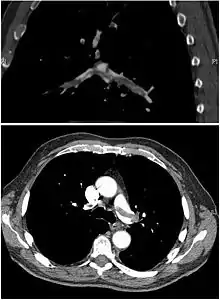

Спіральна комп'ютерна томографія

Спіральна комп'ютерна томографія за методикою проведення та затратами є більш простішим обстеженням та рівнозначним по інформативності з селективною контрастною ангіопульмонографією. Цей метод дозволяє виявляти тромби безпосередньо у просвіті судин. Чутливість односпіральної КТ становлять близько 70 %, а специфічність — 90 %. Впровадження в клінічну практику мультиспіральної КТ дозволило підвищити чутливість обстеження до 83 %, а специфічність до 96 %.[14] На думку групи експертів Європейського товариства кардіологів, для хворих з високим ризиком ТЕЛА достатньо проведення односпіральної КТ, а для хворих із низьким та середнім ризиком ТЕЛА необхідне проведення мультиспіральної КТ для більш точної верифікації діагнозу.[15]